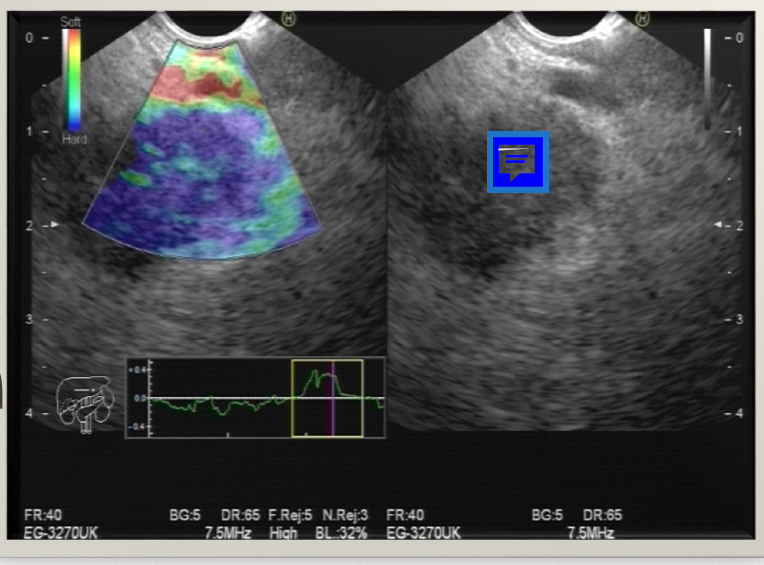

מהו הממצא

A

פסואודוציסטה בלבלב- דם,אפיתל ושאריות של חלבון שהצטבר

How well did you know this?